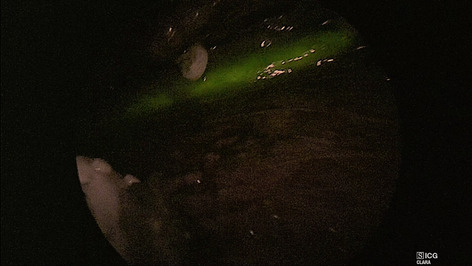

Introduction: Real-time physiologic imaging is an inevitable necessity to improve clinical outcomes. Today, indocyanine green (ICG) is commonly used for intraoperative assessment of tissue perfusion, however, its use is complicated by: (1) pharmacokinetics and user interpretation variance; (2) workflow inconvenience; and (3) capital costs. Laser speckle contrast imaging (LSCI) uses coherent laser light to show perfusion in open surgery, but no form-factor exists for MIS use (laparoscopic or robot-assisted). We report an interim analysis of the first multi-center usability and utility clinical trial using a dye-less technology, and real-time relative quantification of tissue perfusion from preclinical studies.

Methods: ActivSightTM, an FDA-cleared device, consists of an imaging module (an adapter positioned between any white light camera and laparoscope) and a light engine. LSCI detects tissue perfusion without an external fluorophore and displays it to the surgeon as a color heatmap. ActivSightTM also visualizes ICG using near infrared fluorescence (NIRF). Usability was determined using human factor testing on a Likert scale (1–5) while utility was measured by comparing perfusion detection between ICG and LSCI modes (without fluorophore). Accuracy of ICG and LSCI perfusion display was determined in user post-hoc survey comparing white light, ICG, and LSCI intraoperative images from sleeve gastrectomies. Relative quantification was measured in co-axial spotlighted areas, translating a perfusion heatmap to numerical values using proprietary algorithms.

Results: 66 consecutive patients undergoing elective MIS colorectal, bariatric surgeries, and cholecystectomies (LC) (Table 1) between 11/2020 and 07/2021 were enrolled (NCT#04,633,512). Usability evaluation (n = 22 surgeons) demonstrated: display quality of 4.07 + 0.86; ease of setup 4.26 + 0.85; and form-factor 3.82 + 1.57; and weight 3.73 + 1.10. No adverse events occurred in patients, surgeons, or systems (Table 1). Perfusion boundaries (Fig. 1A–D) on post-hoc surveys (n = 10) were concordant between intraoperatively identified boundaries (ground truth) and LSCI images (p = 0.329), and significantly discordant with ICG images detected within two minutes of first ICG injection (p = 0.043). After multiple ICG injections, residual ICG was detected in non-perfused tissue (Fig. 1E). This false-positive display was absent when using LSCI (Fig. 1F). In porcine models, relative perfusion units obtained using LSCI (Fig. 1I–L) were significantly higher in vascular vs non-vascular tissue (294.41 vs 35.08, p < 0.0001).